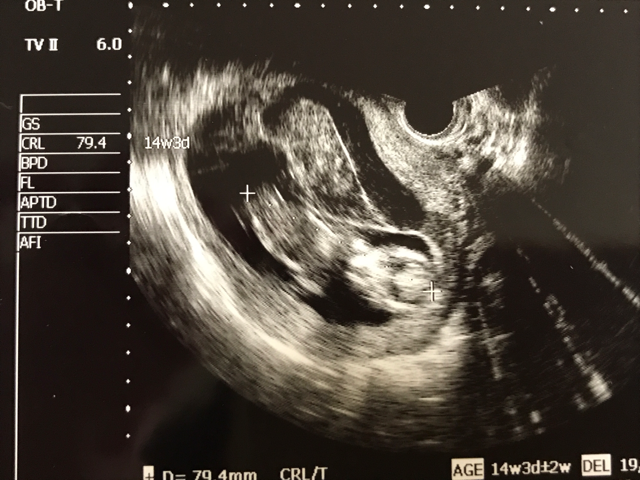

妊娠14週 3 6日 のエコー写真 体験談

妊娠14週 0 2日 のエコー写真 体験談

妊娠14週1日 14w1d の超音波 エコー 写真

妊娠14週6日 14w16d の超音波 エコー 写真

妊娠14週目 14w0d 6d のエコー写真とエピソード 妊娠4ヶ月 Cozre コズレ 子育てマガジン